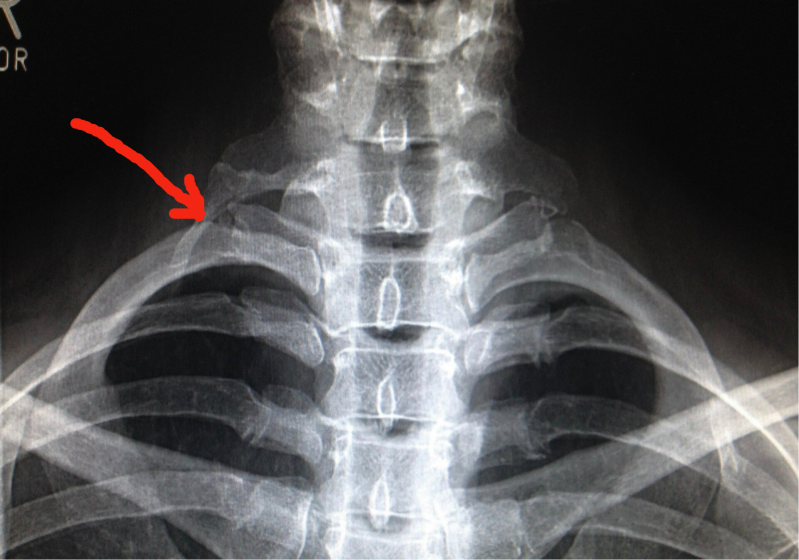

Halsrippen sind die bekanntesten potentiellen Verursacher eines Thoracic Outlet Syndroms, meist mit arterieller Beteiligung, jedoch haben nur etwa 10% der TOS-Patientinnen und Patienten eine solche anatomische Variante.

Weitaus häufiger finden sich prominente Fortsätze des 7. Halswirbels mit oder ohne Halsrippenanlagen, die sich in bandartige Strukturen (s.o., Sibson’s Fascia) fortsetzen, welche ähnlich irritierend wirken wie Halsrippen, aber weniger gut bildgebend darstellbar sind.